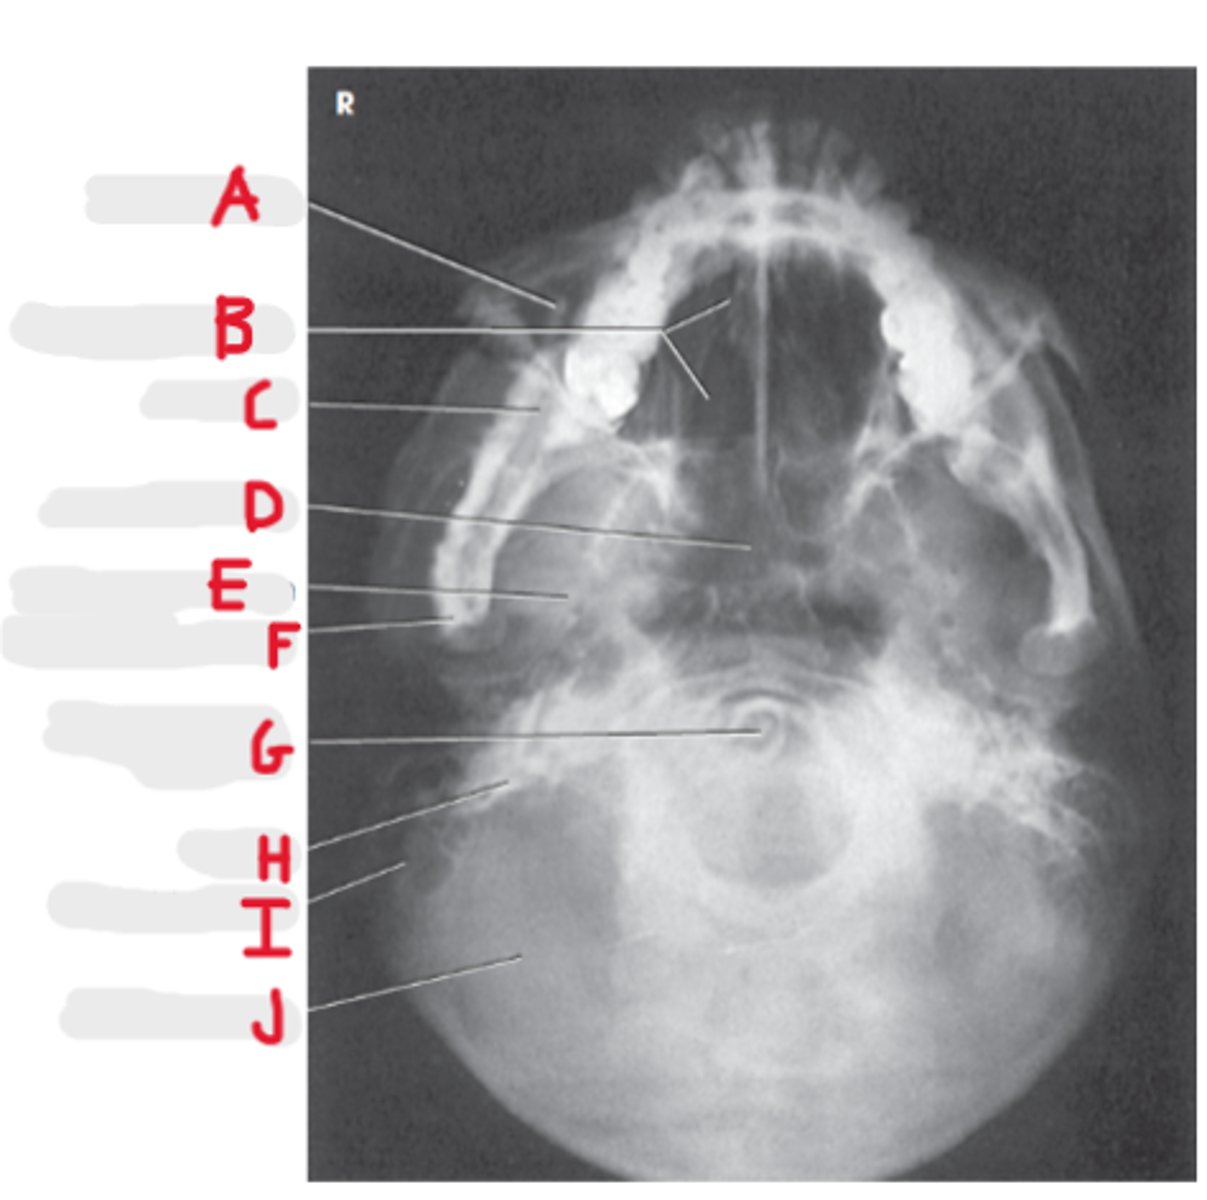

Submentovertex (or vertical) SMV

What projection is this?

CR - perpendicular to IOML

enters 1-1 1/2 inch below the mentum

What is the CR for the SMV?

Infraorbital meatal line (IOML)

What line is parallel to the IR for the SMV?

Basal view because it demonstrates the base of the skull

What is the SMV known as and why?

Sphenoid and ethmoid

What sinuses are best demonstrated on an SMV?

Look for equidistant lateral border of skull to mandibular condyles

How do we look for rotation/tilt on an SMV radiograph?

Maxillary sinus

A

Upper teeth

B

Sphenoid sinuses

C

Lower teeth

D

Parietoacanthial Transoral (Open-Mouth Waters)

Lips-meatal line (LML)

What line is perpendicular to the IR for PA Transoral (Open-Mouth Waters)?

CR exit at acanthion

What is the CR for a PA Transoral (Open-Mouth Waters)?